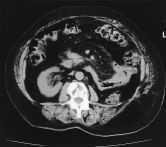

En la Rx PA de tórax(fig. 1) se observa: ausencia radiológica de mama derecha,insuflación del arco anterior y medio de la primera costilladerecha e imágenes similares de menor tamaño en elarco medio de la segunda costilla y arco posterior de laséptima. Afectación del lado derecho del manubrioesternal. En la TAC toraco-abdominal (fig. 2) se aprecia:asimetría de partes blandas, insuflación de laprimera costilla con esclerosis de la cortical ytrabeculación interior moderada, también se objetivaalteración de características similares en manubrioesternal.

Figura2.